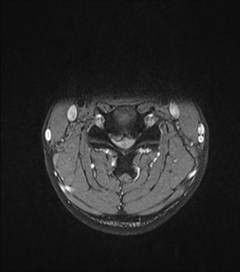

中年男性41岁,因“行走不便2年,加重伴双手麻木2周”之主诉入院,症状主要为:颈部疼痛、僵硬,双下肢无力、行走不稳,双手麻木,协调性差,右手握笔困难。入院查体:步态不稳,C3-C7压痛、叩击痛,肢痛温觉减退,双上肢肢肌力5-级,双下肢肌力4-级,肌张力增高,双下肢腱反射亢进,病理征(+),行颈前路小切口突出椎间盘切除、前路颈椎桥形锁定植骨融合(ROI-C假体),无需前路钢板,术后四肢麻木明显缓解,右上肢精细动作明确增强,可写字,行走不稳消失,肌力基本正常,颈部活动度无明显受限。(图1、图2)

图1:术前颈椎MRI提示颈椎退行性变,C4/5椎间盘突出、脊髓出现高信号改变,C4硬膜囊受压变形。